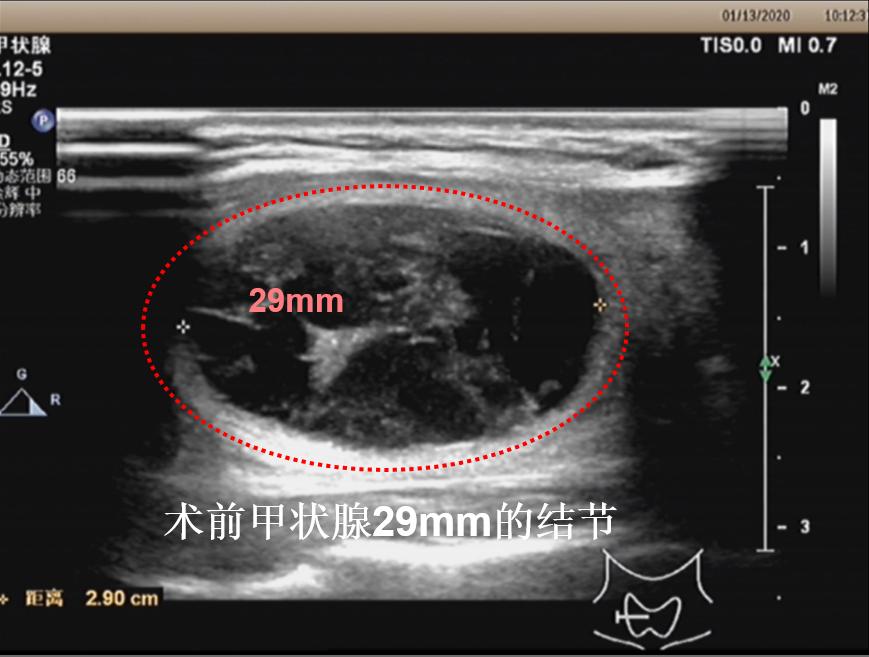

病例①:甲状腺右叶3cm结节消融前后对照,术后体表已触及不到肿物

微创消融前后超声对比,体积缩小93%